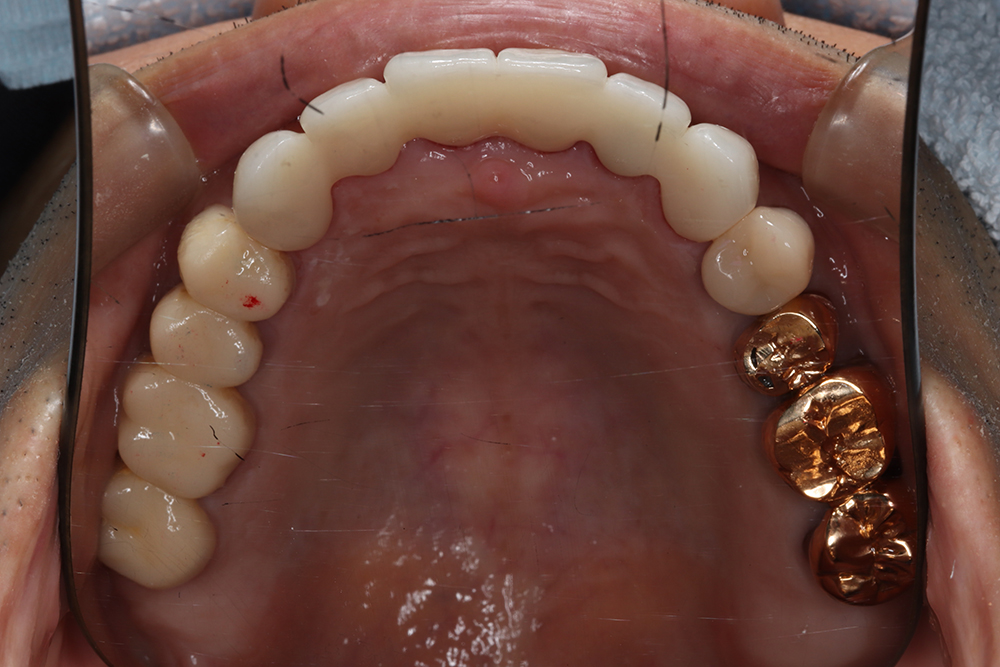

53歳 男性

- 主訴

- 全然噛めない。上の歯が取れてきた

- 処置内容

- 上顎:8本 下顎:2本

- 治療費用

- 上顎:約320万円(税込)、下顎:約160万円(税込)

- 治療期間

-

上顎:1年(仮歯まで8か月)

下顎:8か月(仮歯まで5か月)

- リスク

- 上部構造物、仮歯の破折、術後の腫れ(3日)、人工歯根脱落リスクがあります